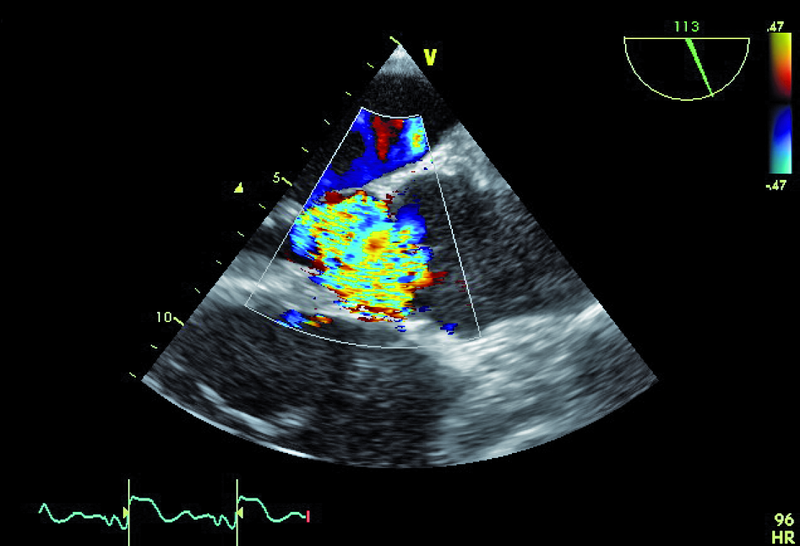

6. Ciężka niedomykalność aortalna (ryc. 4).